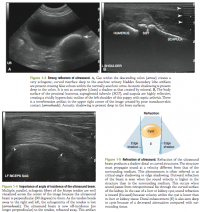

Propagation Artifacts

Attenuation